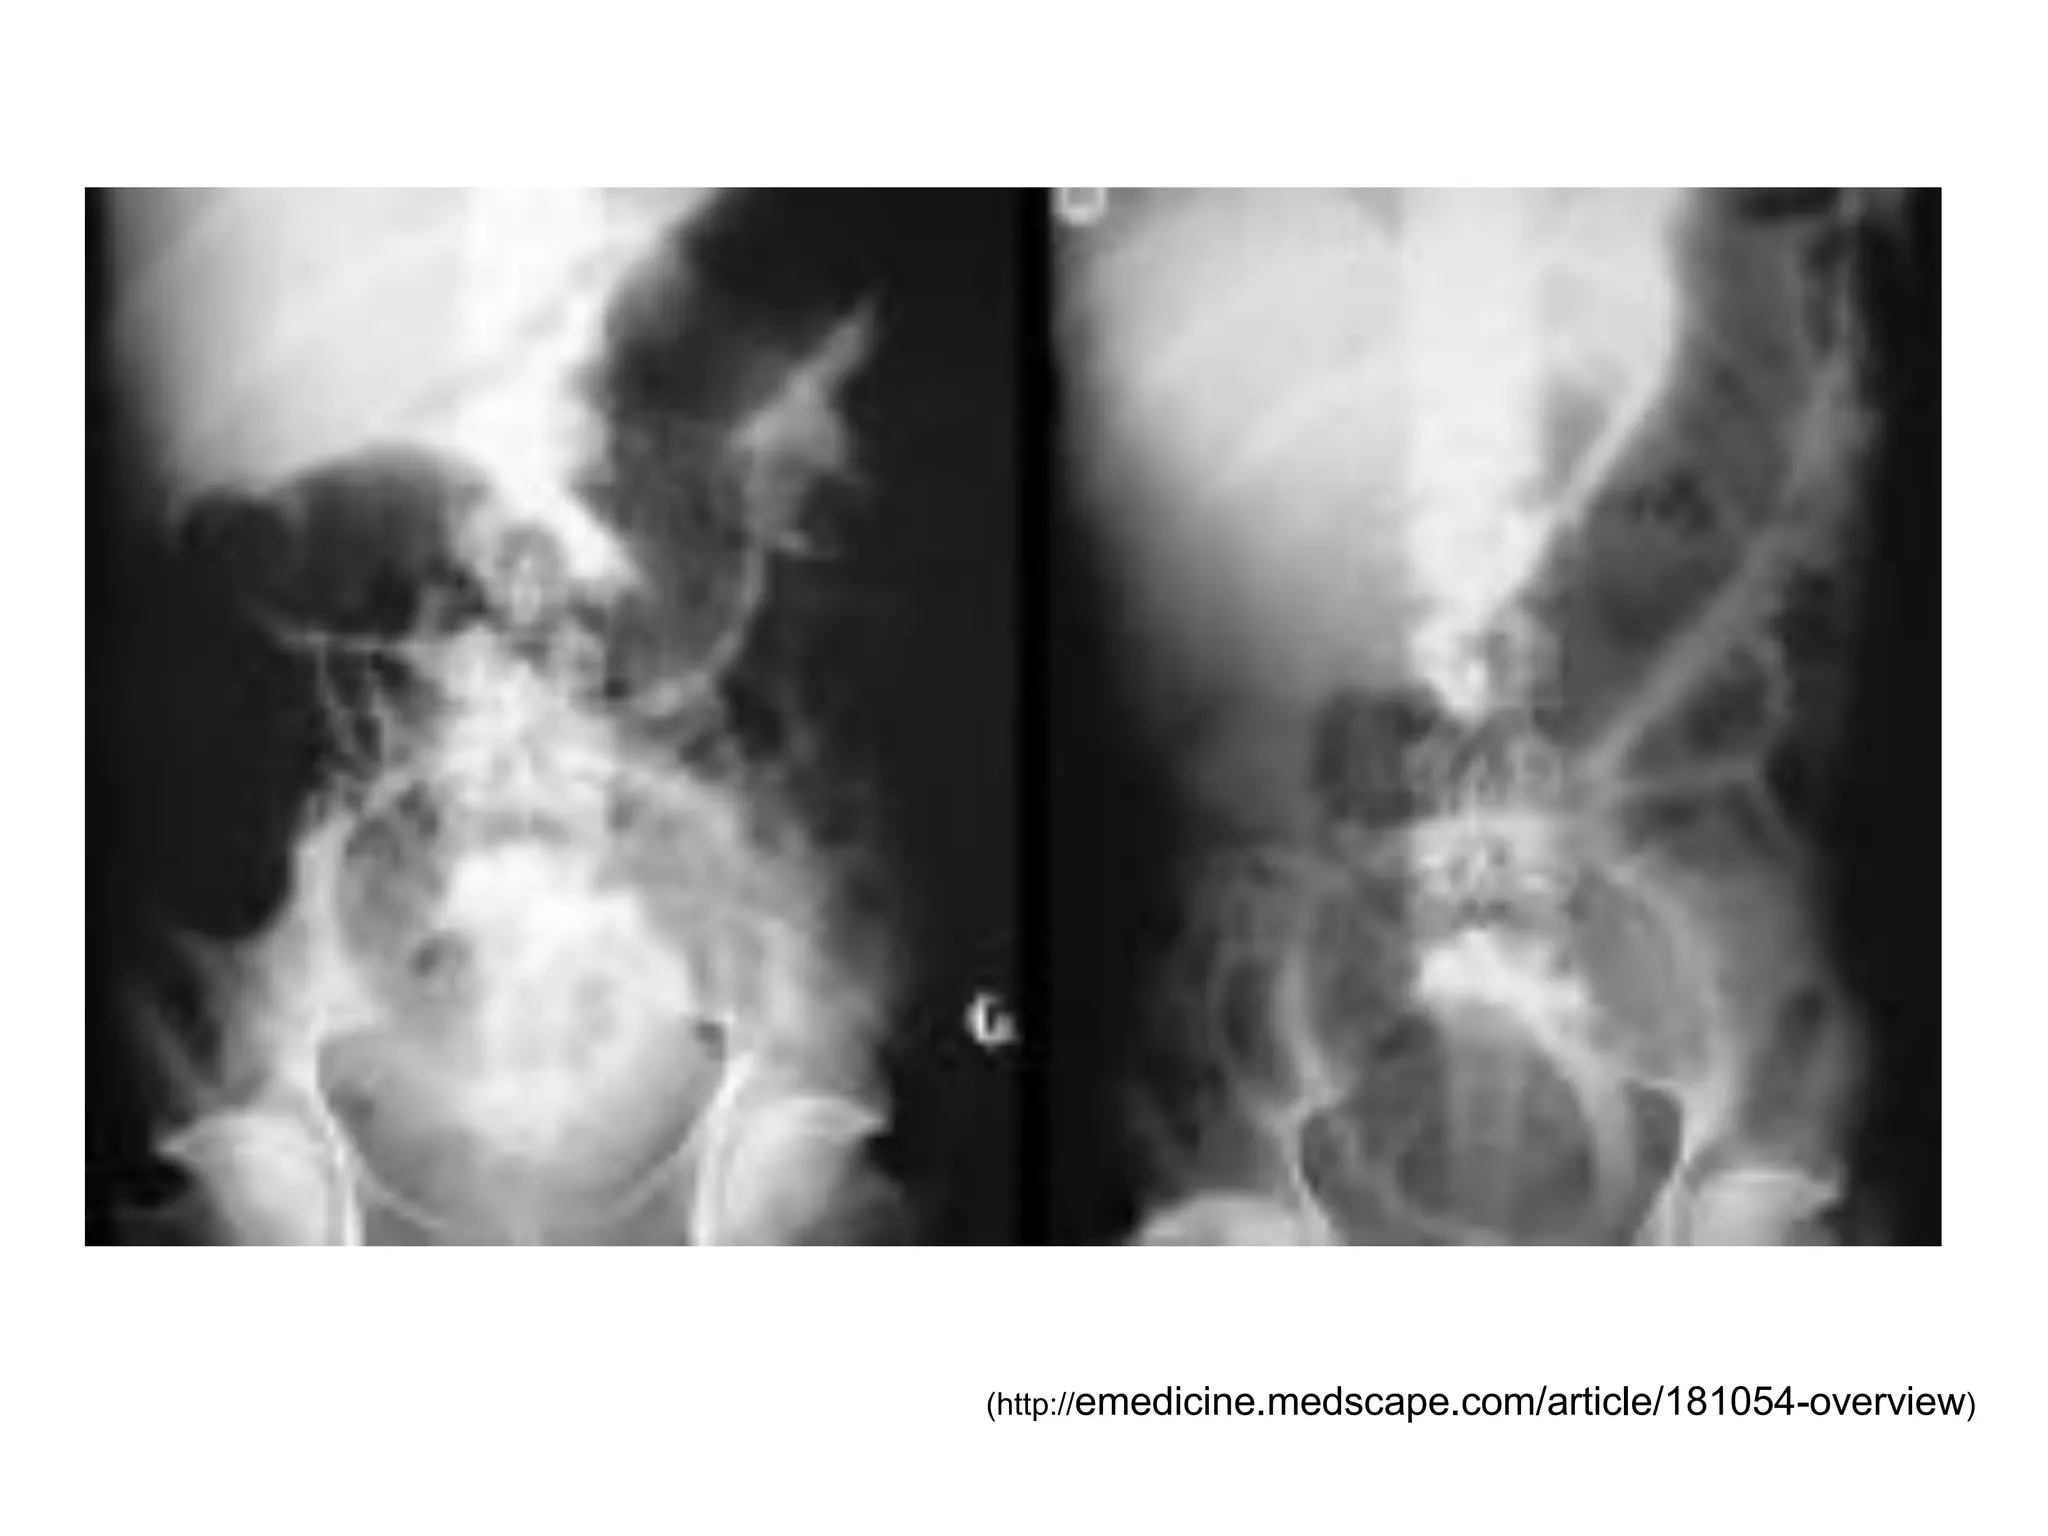

PHÌNH ĐẠI TRÀNG NHIỄM ĐỘC

(Toxic megacolon)

TC nhiễm độc toàn thân: với ≥ 3 / 4 triệu chứng

Sốt ≥ 38o5C

M > 120 lần / phút

BC > 10,500/mm3

Thiếu máu

Kèm ≥ 1 / 4 triệu chứng

Rối loạn tri giác

Tụt huyết áp

Dấu hiệu mất nước

Rối loạn điện giải

Kèm dãn ĐT trên XQ (kinh điển d ĐT ngang ≥ 6cm)

(http://emedicine.medscape.com/article/181054-overview)